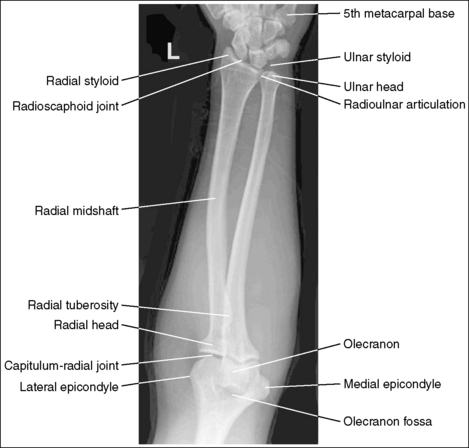

The distal and proximal forearm is positioned in an AP projection. The radial styloid is demonstrated in profile laterally, and superimposition of the metacarpal bases and of the radius and ulna is minimal.

The ulnar styloid is projected distally to the midline of the ulnar head.

The proximal forearm is positioned in an AP projection. The radial head is superimposed over the lateral aspect of the proximal ulna by approximately 0.25 inch (0.6 cm). If included on the IR, the medial and lateral humeral epicondyles are demonstrated in profile at the extreme medial and lateral edges of the distal humerus.

The capitulum-radius joint is either partially or completely closed, and the radial head articulating surface is demonstrated. The olecranon process is situated within the olecranon fossa, and the coronoid process is visible on end.

The radial tuberosity is demonstrated in profile medially, and the radius and ulna appear parallel.